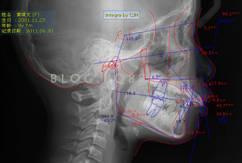

下面這個(gè)小患者就存在需早期矯正的問題。通過早期矯正,在不長(zhǎng)的時(shí)間內(nèi)就達(dá)到極為明顯的療效。她的情況如果等到牙齒替換完畢后再解決,矯治的難度則會(huì)非常大。

部分早期矯正裝置